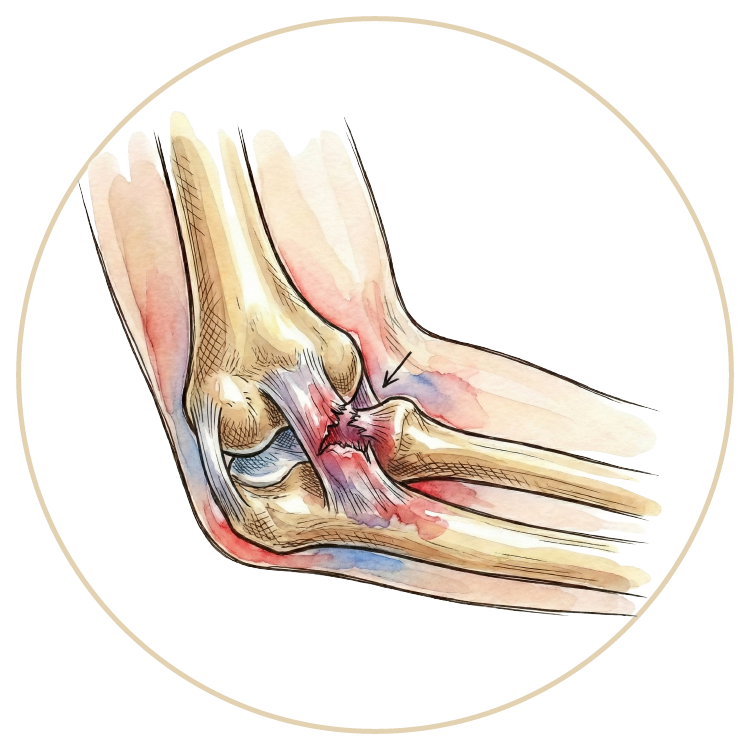

Dirsek Yaralanmaları

Dirsek Artroskopisi

Dirsek Protezi